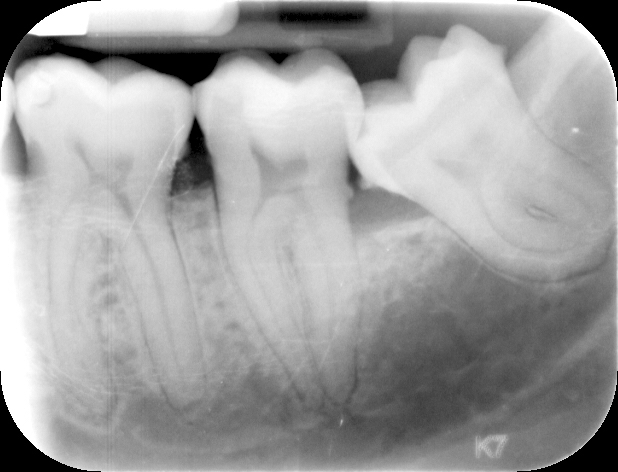

avevo tutti e 4 i denti del giudizio, i 2 superiori li ho tolti senza difficoltà, quelli inferiori purtroppo sono disposti quasi orizzontalmente e sono vicini al nervo.

I denti NON mi fanno male, ma dato che non credo di poterli tenere fino alla morte e sono indubbiamente difficili da pulire in quella posizione (in più mi sembra ci sia un certo abbassamento osseo) preferirei toglierli. Non è stata un scelta del dentista ma mia.

Allego Rx, valutazione del radiografo e cone beam 3D (me lo sono scaricato sul pc quindi posso avere tutte le immagini che voglio nel caso servissero)

Buongiorno, ho visto tutte le immagini e mi chiedo se sia il caso, in assenza di patologia, di intervenire.Dal punto di vita radiografico non vedo grosse difficoltà, il dubbio è sull'opportunità se non le danno, per ora, problemi.

Buongiorno. Radiograficamente non ci sono problemi. Non esiterei ad estrarlo quanto prima, visti i rapporti col II molare.